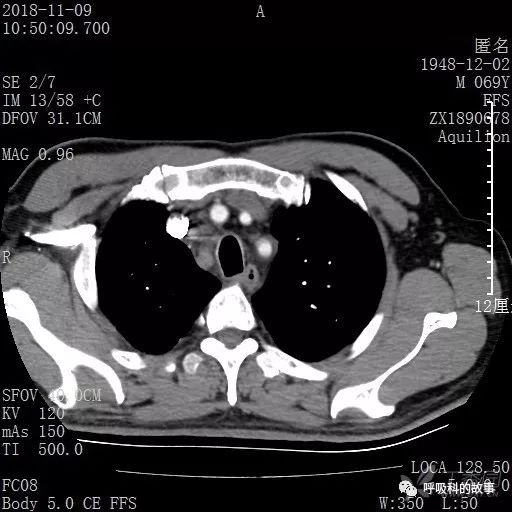

胸部增强CT示右肺门占位伴远端阻塞性肺炎,纵膈、右肺门、右侧颈根部、右侧腋下及肝门部肿大淋巴结。两侧胸腔少量积液。

肺窗CT